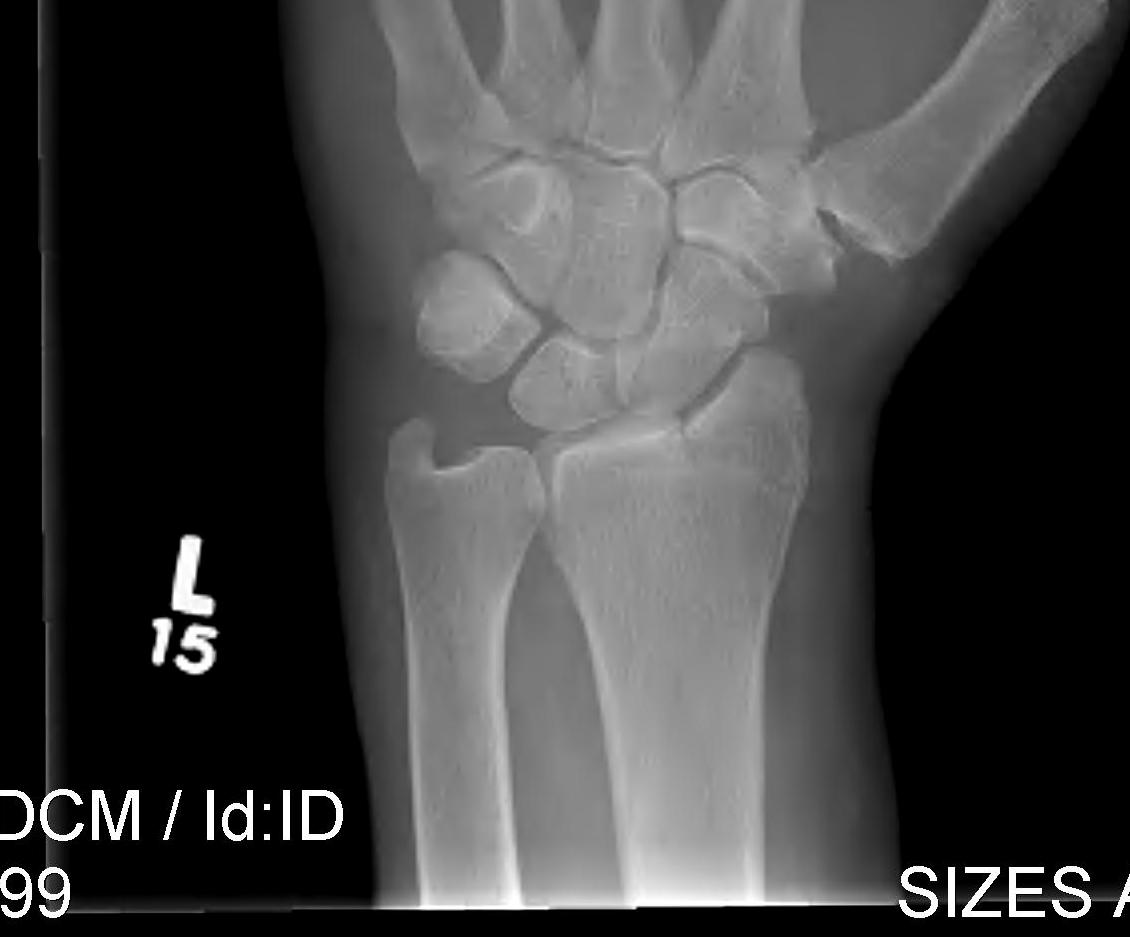

Radial angles

Volar tilt mean 11° Radial inclination  mean 22° Radius mean 11 mm longer than ulna